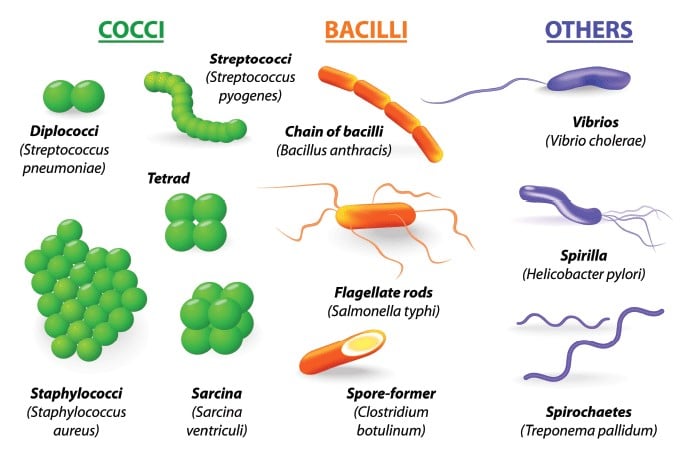

Klasifikasi Bakteri Berdasarkan Bentuk, Pewarnaan Gram, Suhu Dan Kebutuhan Oksigen Lengkap | RuangBiologi.Co.Id

Klasifikasi Bakteri Berdasarkan Bentuk, Pewarnaan Gram, Suhu Dan Kebutuhan Oksigen Lengkap | RuangBiologi.Co.Id

Bentuk Bakteri : Pengertian, Contoh Dan Gambarnya Lengkap | RuangBiologi.Co.Id

Bentuk Bakteri : Pengertian, Contoh Dan Gambarnya Lengkap | RuangBiologi.Co.Id

Biologi Kelas 10 | Apa Saja Dasar Pengelompokan Bakteri?

Biologi Kelas 10 | Apa Saja Dasar Pengelompokan Bakteri?

5 Cara Pengelompokan Bakteri | idschool

5 Cara Pengelompokan Bakteri | idschool